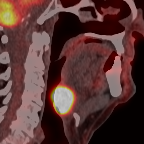

This paper presents an overview of the second edition of the HEad and neCK TumOR (HECKTOR) challenge, organized as a satellite event of the 24th International Conference on Medical Image Computing and Computer Assisted Intervention (MICCAI) 2021. The challenge is composed of three tasks related to the automatic analysis of PET/CT images for patients with Head and Neck cancer (H&N), focusing on the oropharynx region. Task 1 is the automatic segmentation of H&N primary Gross Tumor Volume (GTVt) in FDG-PET/CT images. Task 2 is the automatic prediction of Progression Free Survival (PFS) from the same FDG-PET/CT. Finally, Task 3 is the same as Task 2 with ground truth GTVt annotations provided to the participants. The data were collected from six centers for a total of 325 images, split into 224 training and 101 testing cases. The interest in the challenge was highlighted by the important participation with 103 registered teams and 448 result submissions. The best methods obtained a Dice Similarity Coefficient (DSC) of 0.7591 in the first task, and a Concordance index (C-index) of 0.7196 and 0.6978 in Tasks 2 and 3, respectively. In all tasks, simplicity of the approach was found to be key to ensure generalization performance. The comparison of the PFS prediction performance in Tasks 2 and 3 suggests that providing the GTVt contour was not crucial to achieve best results, which indicates that fully automatic methods can be used. This potentially obviates the need for GTVt contouring, opening avenues for reproducible and large scale radiomics studies including thousands potential subjects.